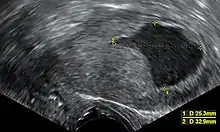

- Accumulation of fluids other than blood or of unknown constitution. One study came to the conclusion that postmenopausal women with endometrial fluid collection on gynecologic ultrasonography should undergo endometrial biopsy if the endometrial lining is thicker than 3 mm or if the endometrial fluid is echogenic. In cases of a lining 3 mm or less and clear endometrial fluid, endometrial biopsy was not regarded to be necessary, but endocervical curettage to rule out endocervical cancer was recommended.[23]